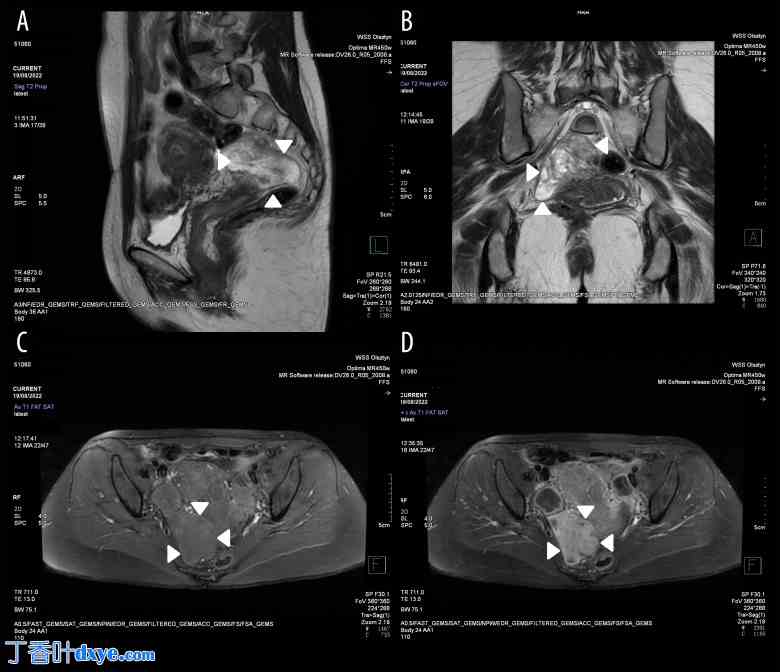

磁共振成像(MRI)显示,右侧卵巢后方(位于双侧子宫侧壁、阴道穹窿和直肠侧壁之间)腹膜后间隙内有一边界清晰、内部信号不均匀的病变肿块,内侧为髂内血管和梨状肌。肿块大小为71×37×67 mm。肿块边界清晰,呈蒂状,蒂部血管丰富,与双侧子宫后壁相连。T2加权像(T2WI)显示病灶内部信号不均匀,以高信号区为主(图1A、1B)。病灶内可见与肌组织(MT)信号强度相近的中低信号成分,呈分隔状和散在分布。T1加权像(T1WI)显示肿块大部分与肌组织呈等信号,可见少量低信号灶(图1C)。未见出血性改变或脂肪成分。注射对比剂(CA)Clariscan™钆特酸葡甲胺后,肿瘤呈明显强化;仅肿瘤内少量液体区域未见强化(图1D)。弥散加权成像(DWI)信号呈不均匀增高(图2A)。表观扩散系数(ADC)呈不均匀性;实性成分ADC值较低,但病灶信号总体较高,这可能提示细胞密度较低(图2B)。各感兴趣区域(ROI)的肿瘤ADC值介于2.979×10⁻³ s/mm²至1.306×10⁻³ s/mm²之间,平均值为2.258×10⁻³ s/mm²(图2B)。未见周围组织浸润(图1A-1D)。检查未发现淋巴结肿大。

图 1.

T2 加权和 T1 加权图像表现。(A) 矢状位 T2 加权 (T2WI) 图像显示盆腔内异质性高 T2 信号肿瘤。(B) 冠状位 T2 加权 (T2WI) 图像显示盆腔内异质性高 T2 信号肿瘤。(C) 轴位 T1 加权 (T1WI) 脂肪抑制图像显示肿瘤内部均匀的中等 T1 信号。(D) 轴位 T1 加权 (T1WI) 脂肪抑制增强图像显示肿瘤内部异质性强化。